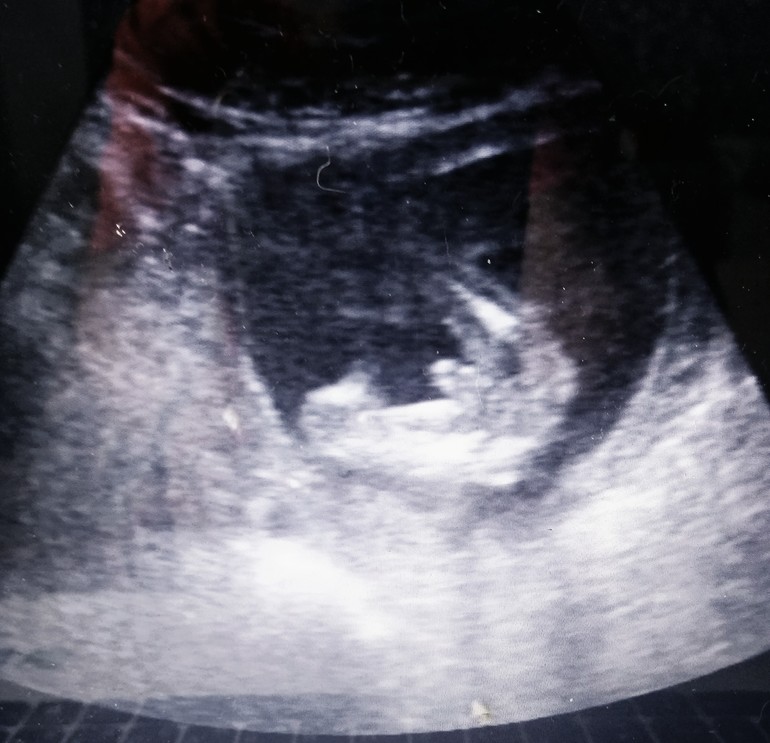

17.03.2018 - сегодня 16недель и 1 день. Были на УЗИ. 100% мальчик))) рост 13 см, вес 157 грамм. Лежит, ножками дрыгает)))

P.S. наше первое фото ню 😂